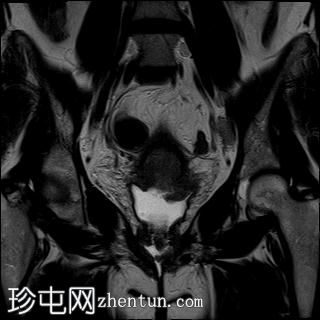

冠状位

T2加权像

可见局部晚期浸润性内生型宫颈癌,肿瘤大小为30 x 32 x 48 mm。该肿瘤已侵犯宫颈前唇和后唇的深层间质,以及子宫肌层的下段。

此外,肿瘤还累及宫旁组织。影像学检查发现异常淋巴结肿大,最大短轴直径(SAD)为10 mm,位于髂总血管分叉处和髂内动脉链下方。该淋巴结肿大在弥散加权成像(DWI)上显示水限制,且增强扫描后可见强化。

影像学检查结果提示根据FIGO分期系统,患者为宫颈癌IIIC1期。